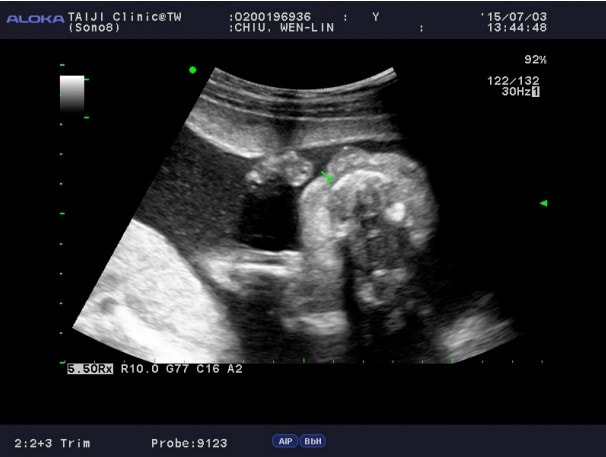

這兩張照片都是高層次的照片,下面這張在看的時候,愷愷喊很大聲:吼~~吃手手會得腸病毒。

哈哈哈哈,有沒有這麼可愛啦!